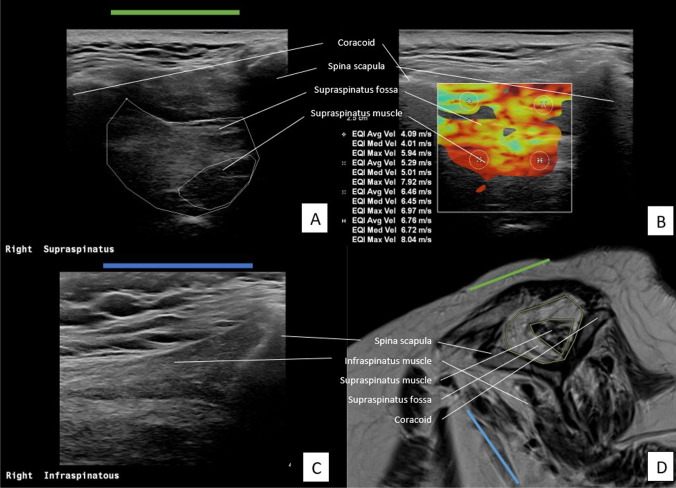

Fig. 1.

Assessment of SSP and ISP muscle on US and MRI of a patient with severe muscle atrophy and fatty infiltration of the SSP muscle. A US plane of SSP. B US plane of SSP with measurements of SWV in m/s in four quadrants. C US plane of ISP. D oblique-sagittal plane of MR image to assess SSP and ISP muscle

Imaging protocol US

The Philips EPIQ 7 with a linear transducer (eL18-4) was used to perform the US. The plane that was used in the assessment of MRI/CT scans was reproduced with the transducer. There where the SSP muscle is at the level of the most prominent muscle contour in an anteroposterior direction. A visualisation of the transverse plane (in relation to the long axis of the muscle) was achieved by turning the transducer perpendicular to the long axis of the muscle belly. In this plane the fossa–muscle ratio was calculated and SWVs were measured [18]. Images A and B in Figs. 1 and 2 show the US plane used to assess the SSP muscle. The position of the transducer in which the SSP muscle is assessed is shown as a green line.

Using the method by Rosskopf et al [18] the SWV was measured in four quadrants; anterosuperior (A), posterosuperior (B), anteroinferior (C), and posteroinferior (D). Per quadrant velocity in meters per second was measured (Fig. 1B and Fig. 2B). The mean SWV (mSWV) of all quadrants was used for statistical analyses. As Rosskopf et al [18] described, test–retest and interexaminer reliability of the mean of quadrants A and B were excellent. Because of the high reliability of these upper quadrants, the mean of quadrants A and B (AB) was measured and also used in comparison with scan results.

The SSP fossa- and muscle were measured by drawing the surface according to Khoury et al [20] (Fig. 1A and Fig. 2A). The ratio between the cross-sectional area of the SSP muscle belly and that of its fossa was calculated and referred to as the occupation ratio. Visual assessment for grading by Goutallier staging was also applied to the US examination. Therefore, the Goutallier classification was collapsed to a three-point scale. The radiologist performed a visual assessment of the architecture and echogenicity for both the SSP and ISP muscle indicated by ‘Goutallier 0’, ‘Goutallier 1–2’, ‘Goutallier 3–4’, or ‘not assessable’ [13, 14].

Assessment of the ISP muscle (short axis) was obtained by turning the transducer perpendicular to the long axis of the muscle belly, with the scapular spine at the edge of the transducer. The blue line in images C and D in Figs. 1 and 2 indicates the position of the transducer to assess the ISP muscle. Blinded to the interpretation of the scan, US examination was performed by another musculoskeletal radiologist DI, with 9-year experience.